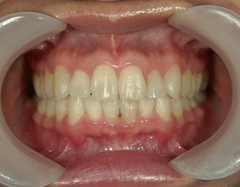

矯正歯科 治療後矯正歯科 プチワイヤー矯正 治療後矯正歯科(プチワイヤー矯正)治療後

矯正歯科 治療後 ミニインプラントを2本埋入し、下顎前歯を圧下